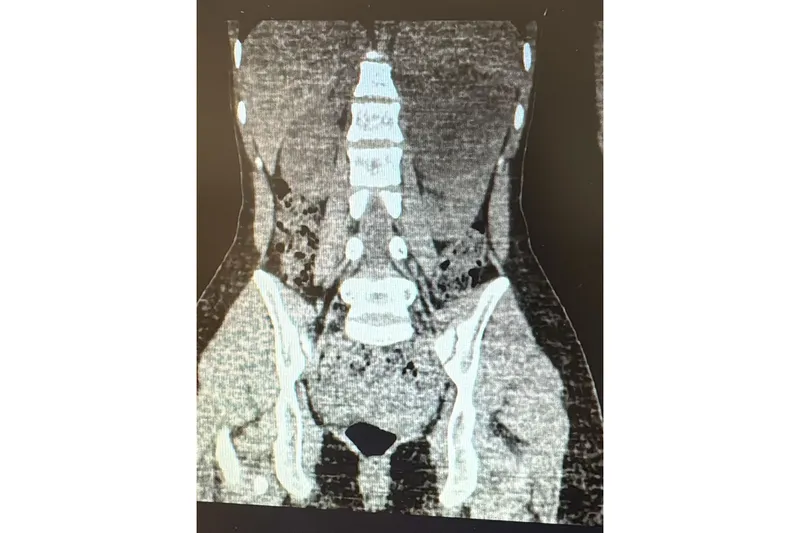

Sol böbreğinde yaklaşık 10 santimetre çapında büyük bir kist tespit edilen 18 yaşındaki kadın hasta, kapalı (laparoskopik) yöntemle gerçekleştirilen başarılı ameliyatın ardından sağlığına kavuştu.

Uzun süredir sol yan ağrısı şikâyeti bulunan hasta, dış merkezde yapılan tetkiklerde sol böbrekten kaynaklanan, böbrek ve dalağı iterek komşu organlara yapışıklık gösteren büyük bir kist saptanması üzerine Viranşehir Devlet Hastanesi’ne sevk edildi. Hastanede yapılan detaylı muayene ve tetkiklerin ardından kistin cerrahi olarak çıkarılmasına karar verildi.

Viranşehir Devlet Hastanesi’nde gerçekleştirilen operasyonda, yaklaşık 10 cm boyutundaki böbrek kisti laparoskopik (kapalı) yöntemle alındı. Ameliyat, 2 adet 5 mm ve 1 adet 10 mm’lik küçük kesi kullanılarak başarıyla tamamlandı. Bu sayede hastanın, büyük boyutlu kistine rağmen açık cerrahiye ihtiyaç duyulmadan tedavi edilmesi sağlandı.